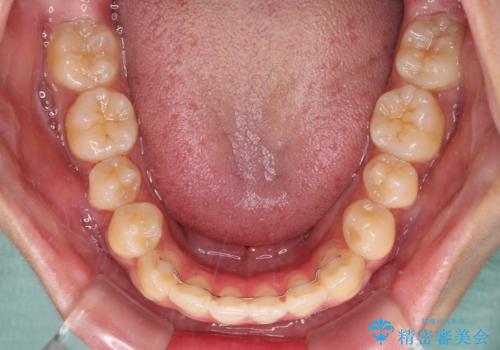

- 前歯の開咬と、受け口による咬み合わせの悪さを気にして来院された患者様です。

上顎歯列が狭窄していたため、急速拡大装置により上顎骨を側方に拡大し、その後ワイヤー装置にて矯正治療を行うこととしました。

舌の突出癖が開咬の原因であったので、改善のための舌トレーニングを行っていただきました。

舌トレーニングは後戻りにも大きく影響するため、とても重要なトレーニングです。